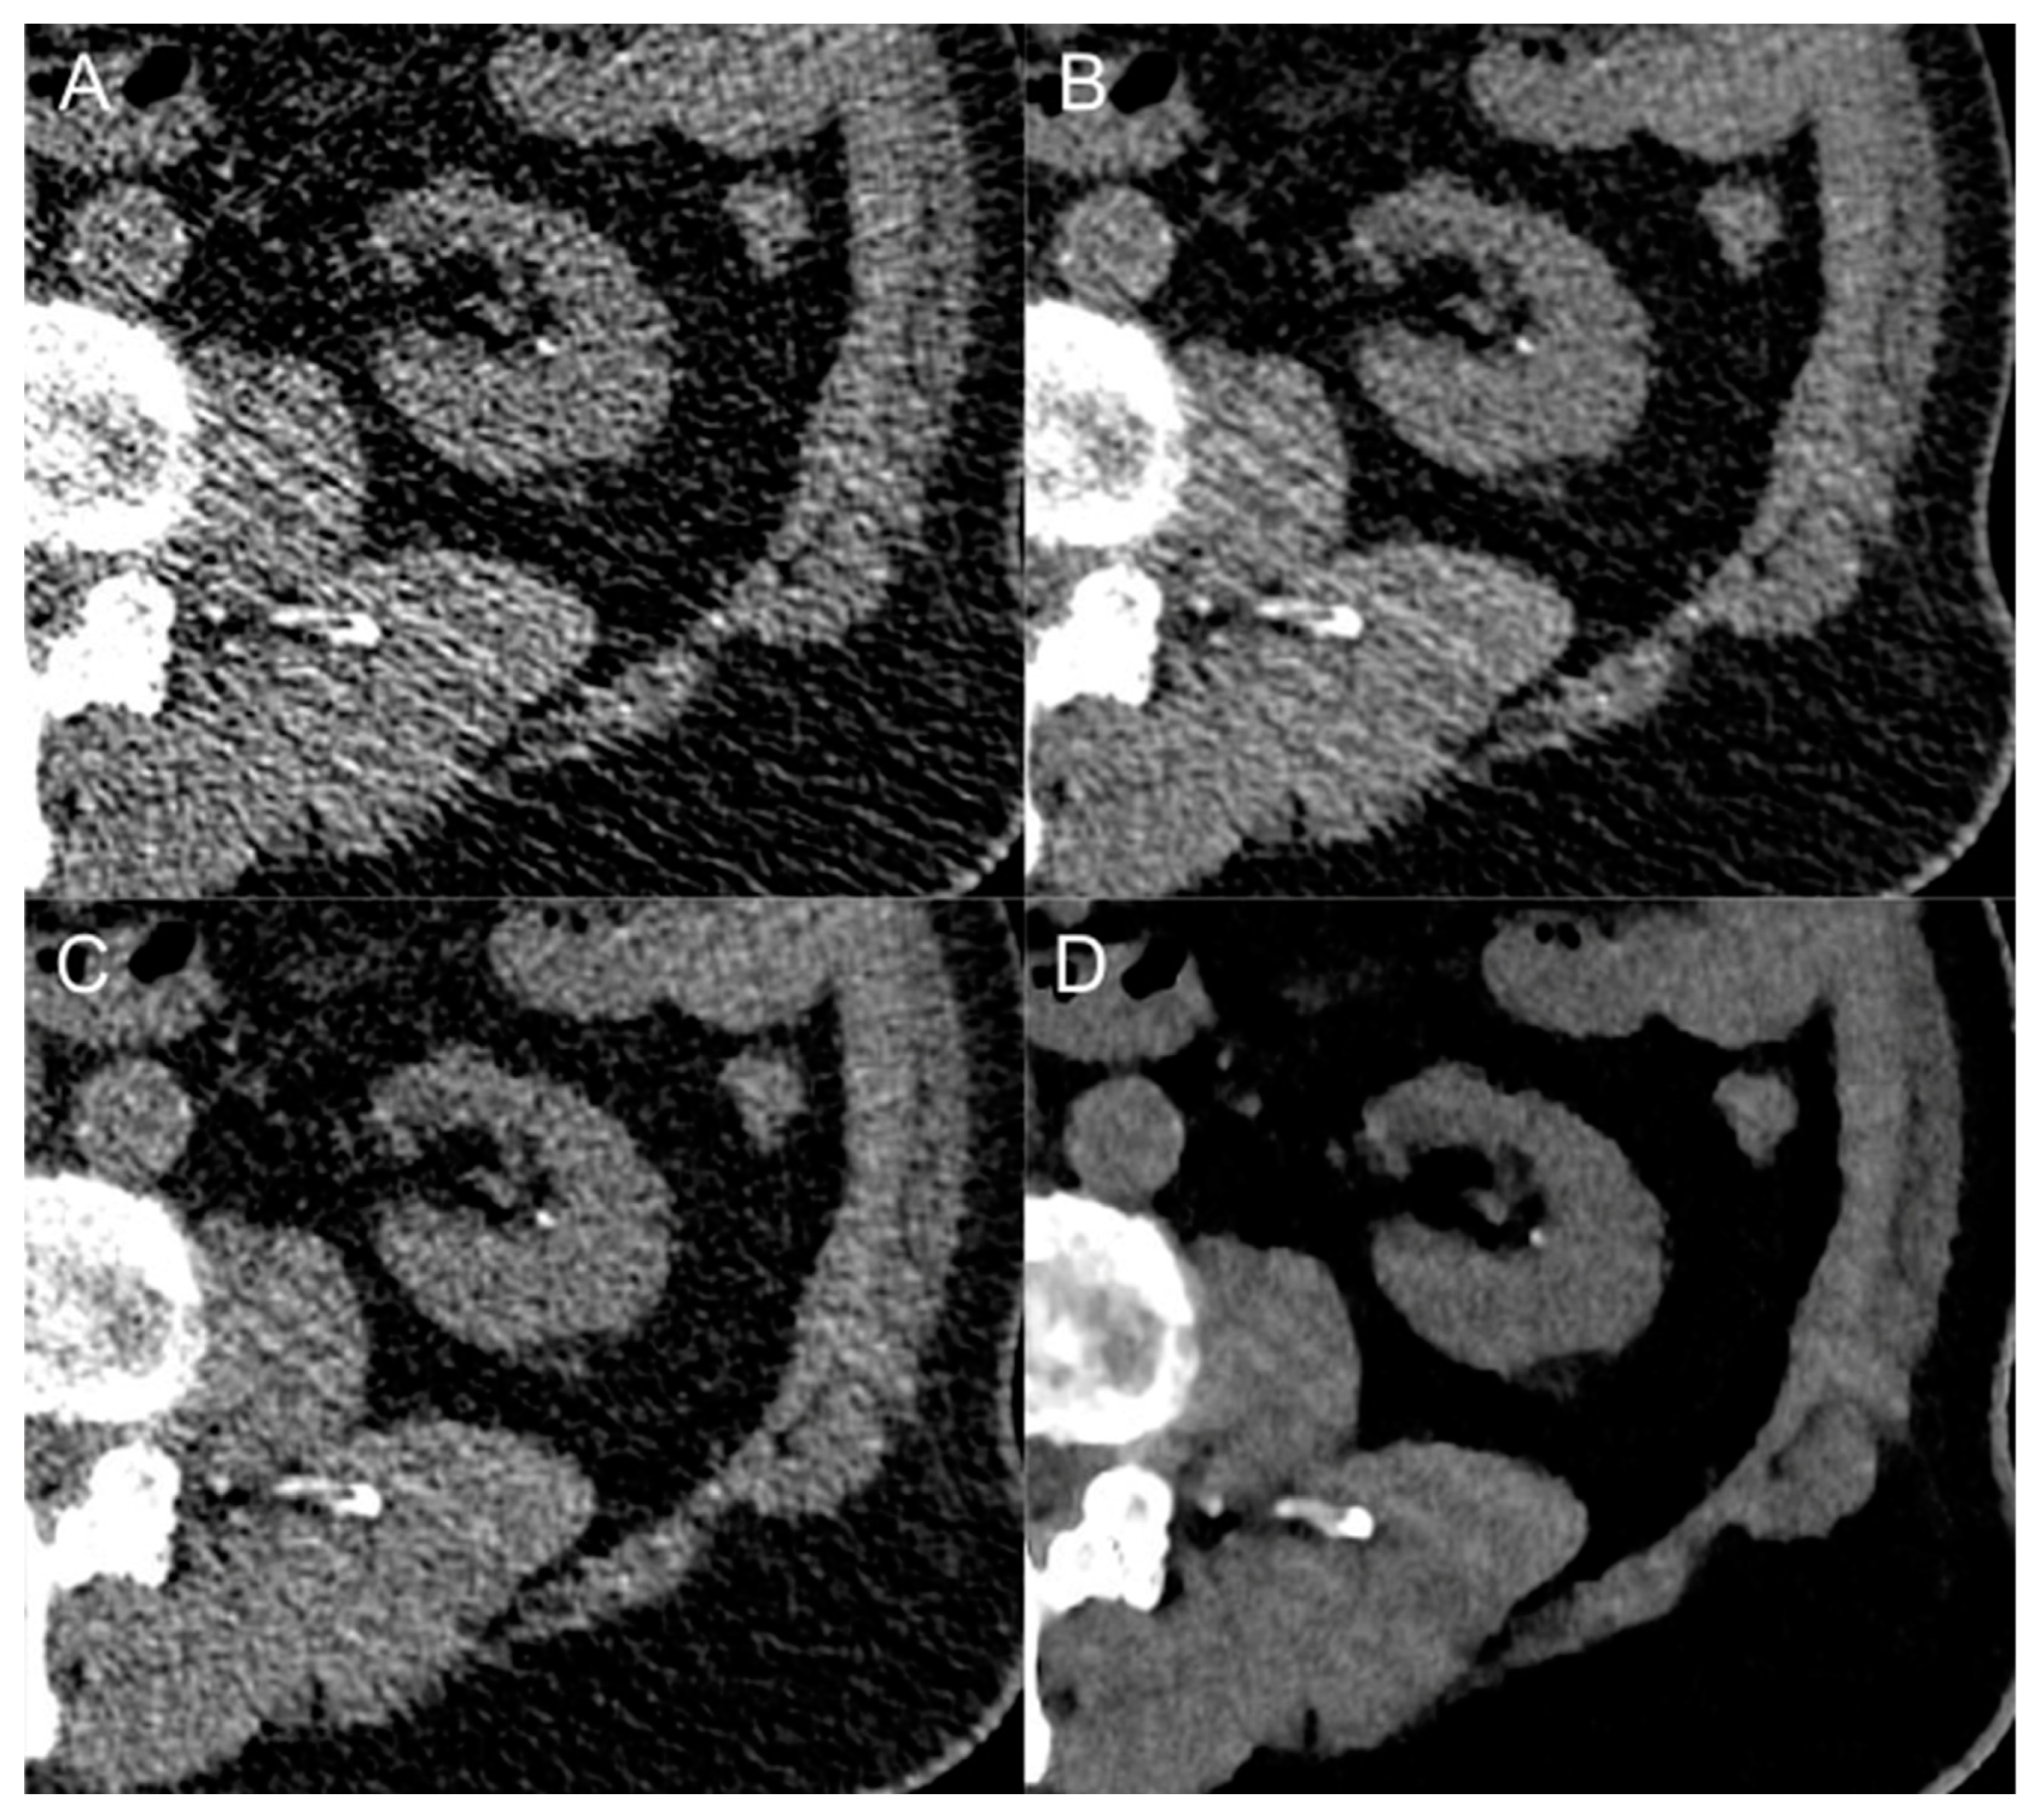

3.4. Urinary Stones

3.4.1. Detection Rate

3.4.2. Stone Size Measurements